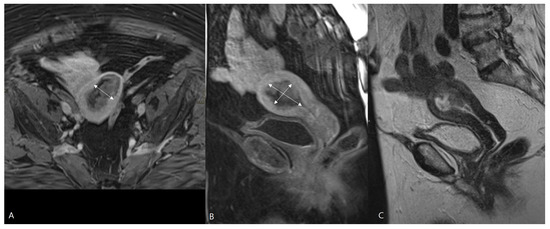

Figure 3.

MRI of endometrial cancer. Sagittal T2-WI (A–C), axial T2-WI (D), axial T1-WI after Gadolinium administration (E) and coronal T2-WI (F). The tumor is extending intraluminal into the left and right cornu (white arrows on (F)). In the cornua, the myometrium is anatomically thinner (short white line in (C,D)) than in the uterine corpus (long white line in (A,D)), which may result in overstaging because intracavitary growth in the cornu (pT1a) may mimic tumor invasion in the outer half of the myometrium (iT1b).